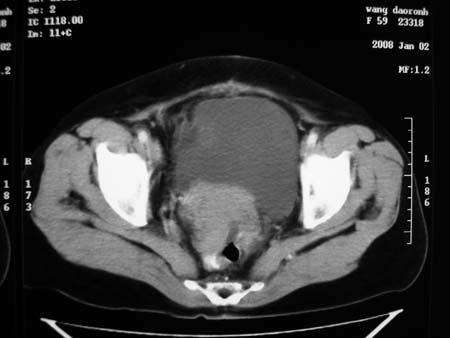

以下是引用卜一在2008-1-2 20:39:00的发言:[br]右侧附件区囊实性肿块,与膀胱壁分界不清,增强后实性部分显示强化。考虑为:右侧卵巢囊腺癌可能性大。支持!

以下是引用zhengfaming在2008-1-2 19:28:00的发言:[br]右下腹腔内附件区可见一囊实性混合密度块影,先考虑囊腺癌